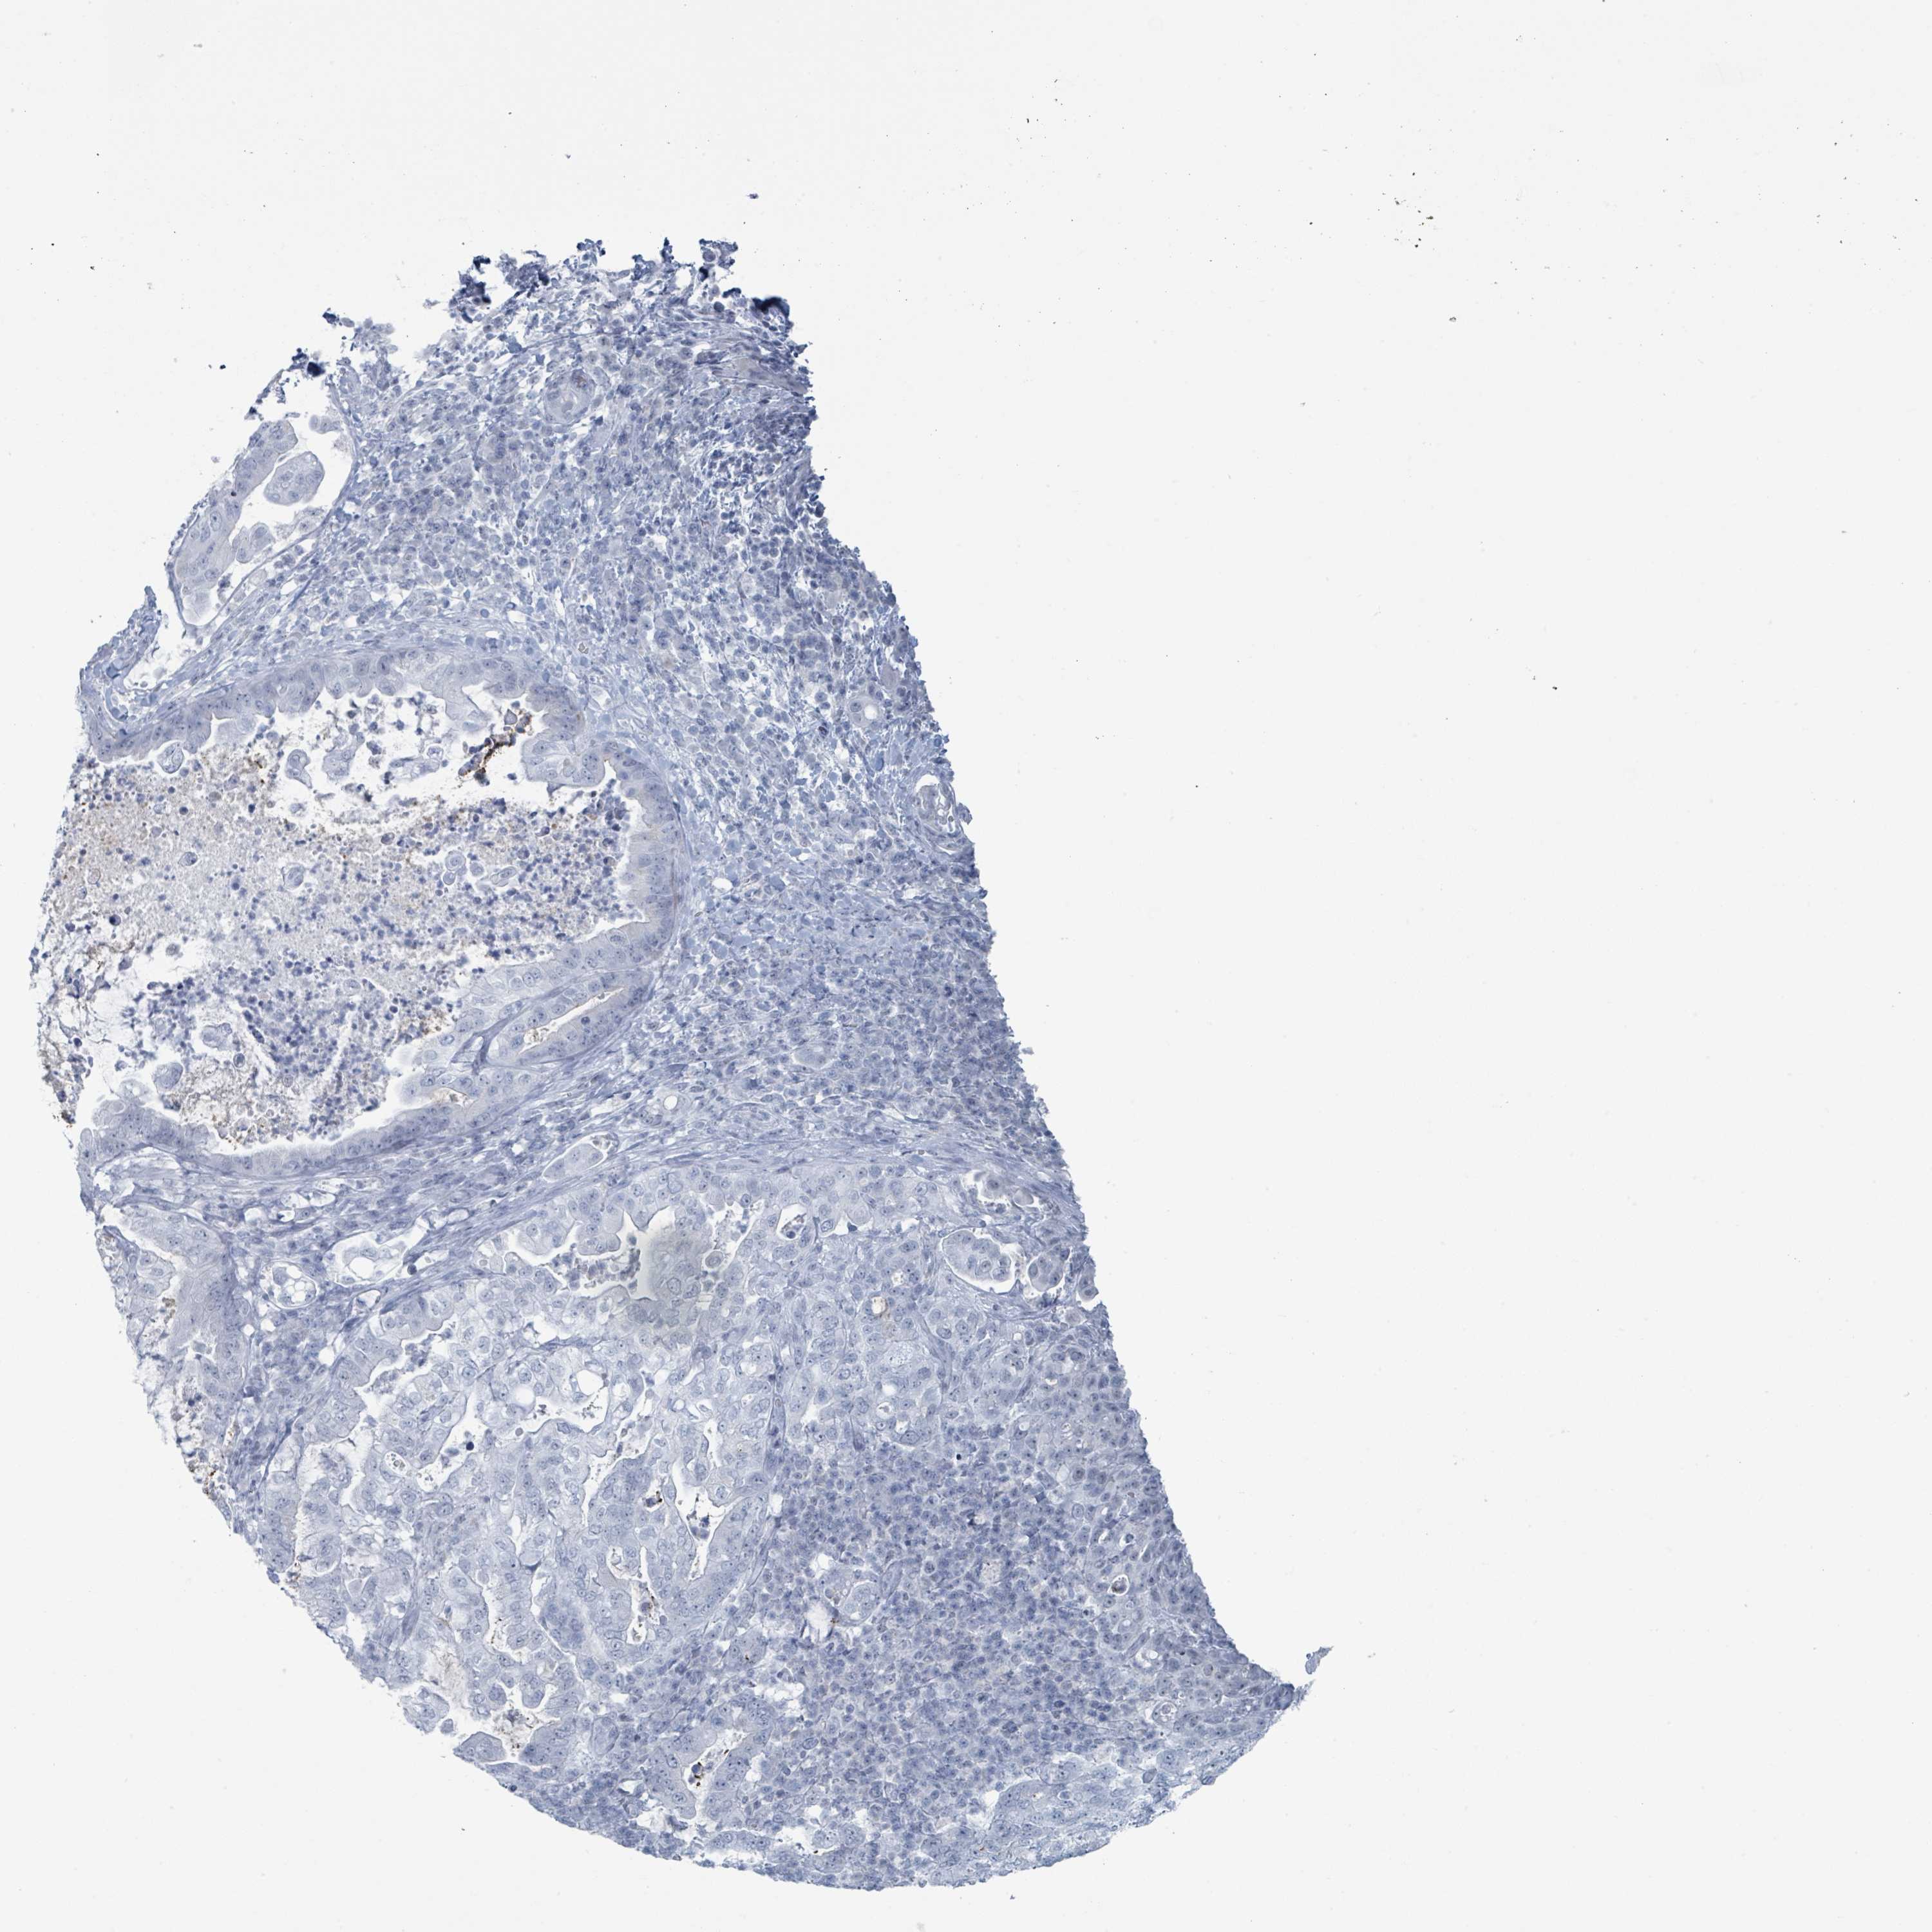

PANCREATIC CANCER - Protein expressioni

A mouse-over function shows sample information and annotation data. Click on an image to view it in a full screen mode. Samples can be filtered based on level of antibody staining by selecting one or several of the following categories: high, medium, low and not detected. The assay and annotation is described here.

Note that samples used for immunohistochemistry by the Human Protein Atlas do not correspond to samples in the TCGA dataset.

Antibody stainingi

Antibody staining in the annotated cell types in the current human tissue is reported as not detected, low, medium, or high, based on conventional immunohistochemistry profiling in selected tissues. This score is based on the combination of the staining intensity and fraction of stained cells.

Each image is clickable and will lead to virtual microscopy that enables deeper exploration of all samples and also displays staining intensity scores, fraction scores and subcellular localization as well as patient and tissue information for each sample.

Antibody HPA050920

Staining

High

Medium

Low

Not detected

Intensity

Strong

Moderate

Weak

Negative

Quantity

>75%

75%-25%

<25%

None

Location

Nuclear

Cytoplasmic/membranous

Cytoplasmic/membranous,nuclear

Adenocarcinoma, NOS